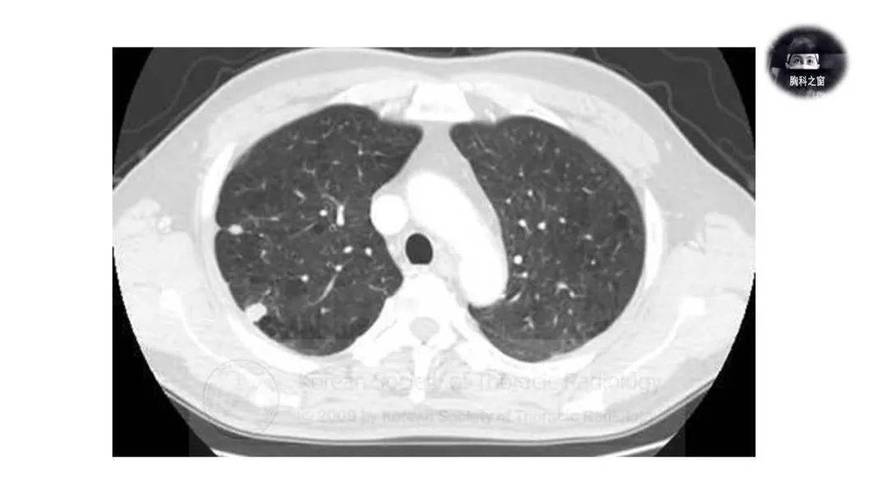

- 影像学表现: 在胸部X光或CT上,它们通常表现为:

- 单发或多发 的圆形或类圆形阴影。

- 边界清晰,密度均匀。

- 大小不一,可以从几毫米到几厘米。

- 好发于肺部的外周(胸膜下区域)。

| 影像学 | 边界清晰的圆形“影子” | 弥漫的网格状、磨玻璃状或蜂窝状阴影 |